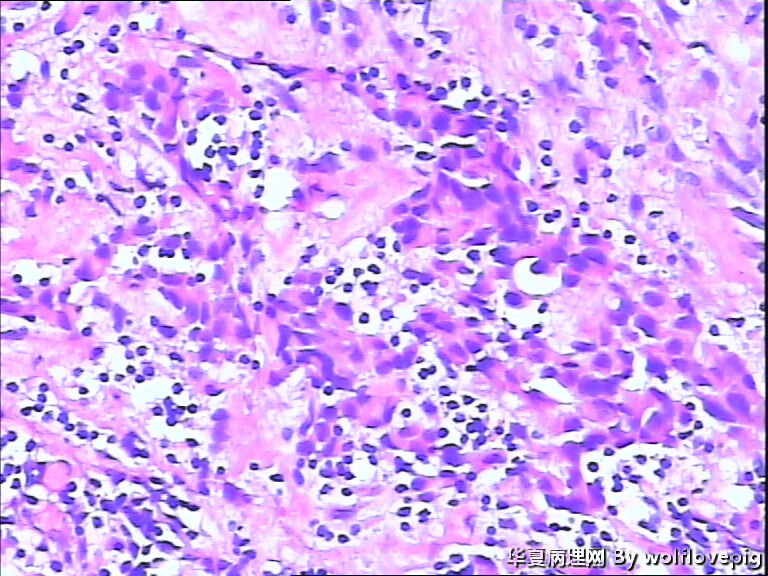

B3937求助!乳腺包块。

女,60y,发现右乳包块6+月。

灰白不整形组织一块:3*2*1.5cm,切面有一灰白区域,边界欠清,质韧。

• 求助!乳腺包块。图1

图1

• 求助!乳腺包块。图2

图2

• 求助!乳腺包块。图3

图3

• 求助!乳腺包块。图4

图4

标签:乳腺浸润性癌

浸润性癌。

浸润性导管癌,最好标记肌上皮。

浸润性导管癌

浸润性导管癌,分化差,除外混合癌(导管癌+小叶癌),免疫组化证实。(本例图像很多,局部炎症反应重,瘤细胞还成合体样无腺管形成似髓样癌,局部似炎性乳癌,局部似小叶癌,呵呵)